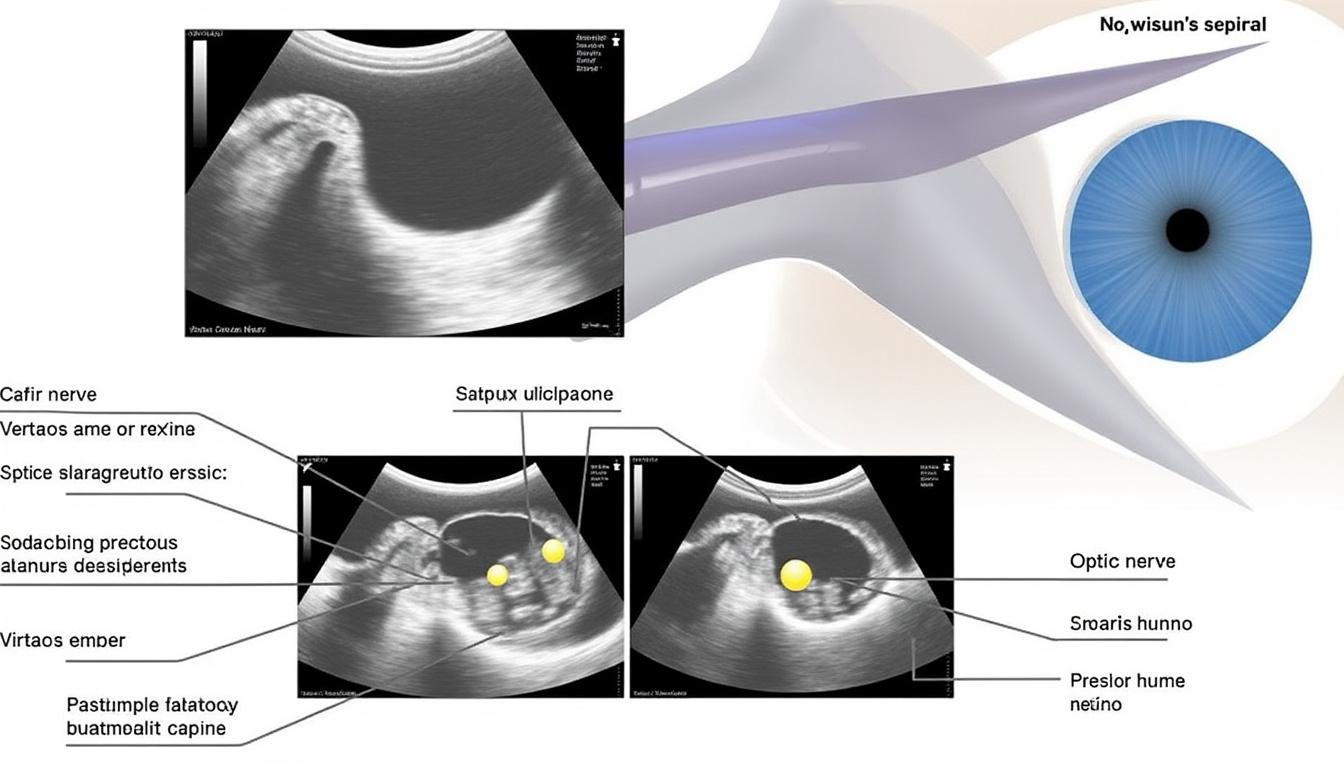

Grâce à l’imagerie ultrasonore B-scan, même un vitré totalement opaque peut être analysé pour déceler des décollements. Cette technique, combinée à l’OCT (tomographie par cohérence optique), contribue à un diagnostic affiné et à une meilleure prise en charge. L’étape suivante décrira en détail ces modalités d’exploration.

L’OCT et l’échographie B-scan

L’OCT fournit une coupe ultrafine de la rétine et de l’interface vitréenne. Cette technologie, inspirée des télécommunications, offre une résolution supérieure à 5 µm. Pour les cas opaques, l’échographie B-scan détecte les décollements ou les masses intraoculaires. Ensemble, ces examens excluent la présence de tumeurs ou d’hémorragies.